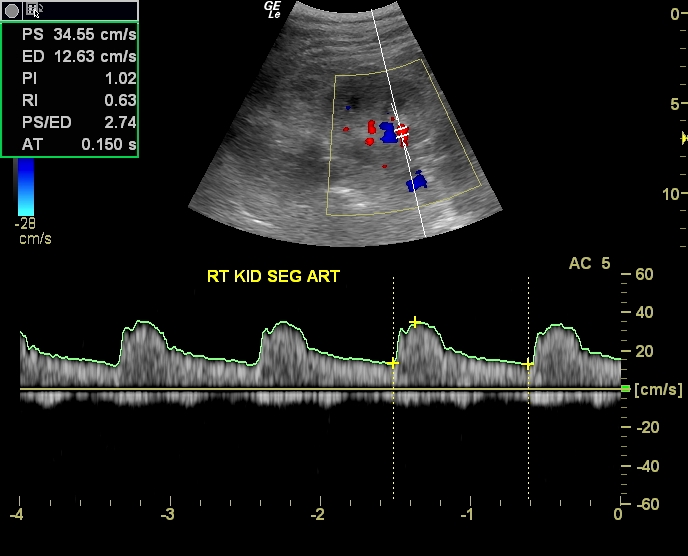

It is performed similarly to a regular ultrasound by placing a probe on the abdomen to. Aorta→ renal artery→segmental artery→interlobar artery→arcuate artery→interlobular arteries→afferent arterioles→glomerulus→efferent arterioles peritubular. The renal arteries are responsible for carrying oxygen-rich blood to your kidneys, which in turn helps the kidneys rid your body of waste and excess fluid.

Renal doppler

Renal artery stenosis (RAS) is a condition in which the arteries that supply blood to the kidneys narrow. The main artery and vein can be readily demonstrated at the renal hilum and should not be confused with a mild degree of. Both ideally are used in conjuction with each other.